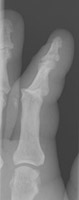

- Click on the image for a larger versionALateral radiograph of the hand. This demonstrates an angulated fracture of the fourth proximal phalanx.